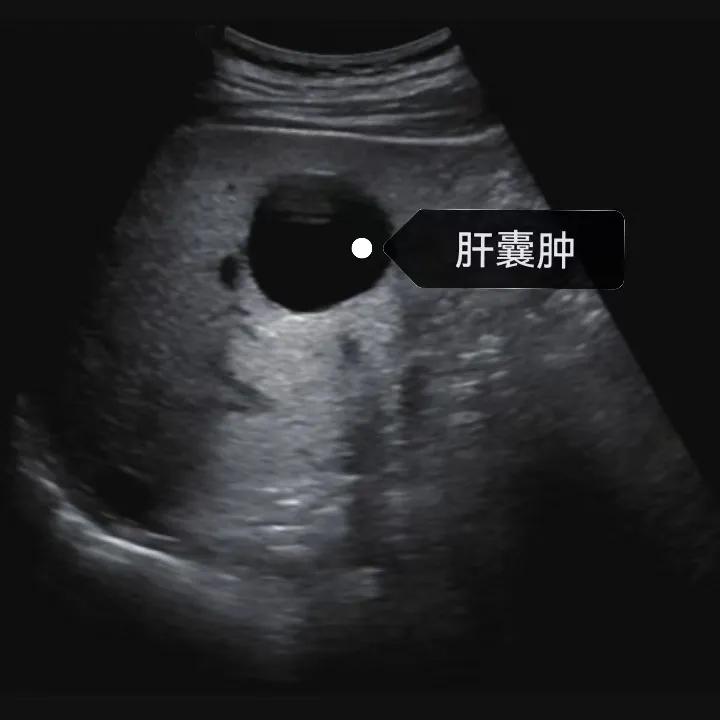

超聲通常是診斷肝囊腫的首選方法,彩超對(duì)肝囊腫的檢出率可達(dá)98%,<1cm的囊腫也可檢出。肝囊腫常表現(xiàn)為圓形或橢圓形無回聲,包膜光滑完整,邊界清晰,可有側(cè)壁回聲失落征象,后方回聲增強(qiáng)。病程長(zhǎng)、囊腫較大者或囊內(nèi)有過出血、感染者,無回聲腔內(nèi)可見少量絮狀回聲漂浮。超聲對(duì)肝囊腫的診斷準(zhǔn)確而靈敏,且方法簡(jiǎn)單、無創(chuàng)、費(fèi)用低、可重復(fù)性高,因此常常被作為首選。